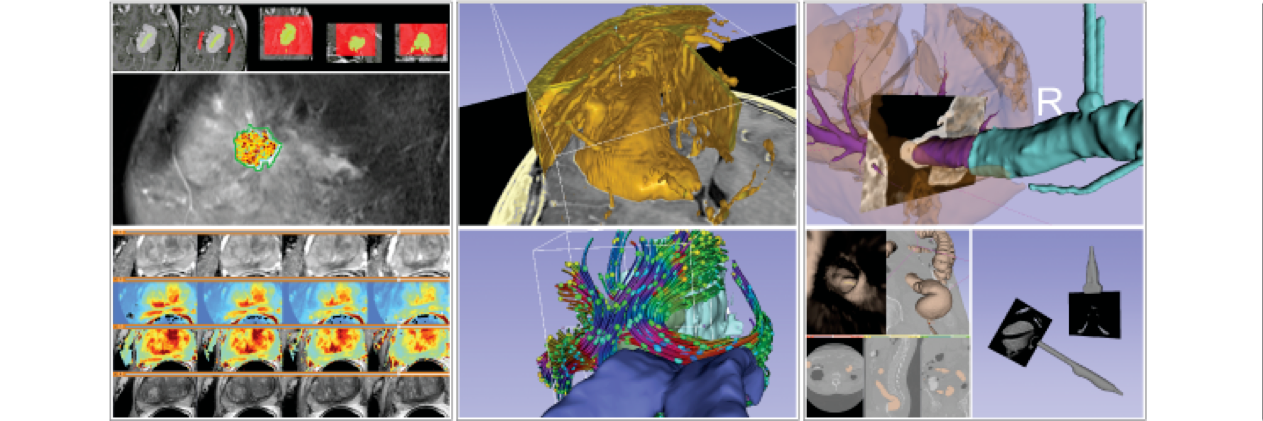

As featured in @NVIDIAGTC, @ProjectMONAI provides a catalytic ML framework for Christian Herz and other @JolleyLab members to derive clinically relevant insights from 3D images of children's hearts. @3DSlicerApp #SlicerHeart youtube.com/watch?v=VN5SOV…

We are thrilled to publish our description of #SlicerHeart, a open source, cardiac-focused image processing extension for @3DSlicerApp that has now been downloaded over 44,000 times. frontiersin.org/articles/10.33…